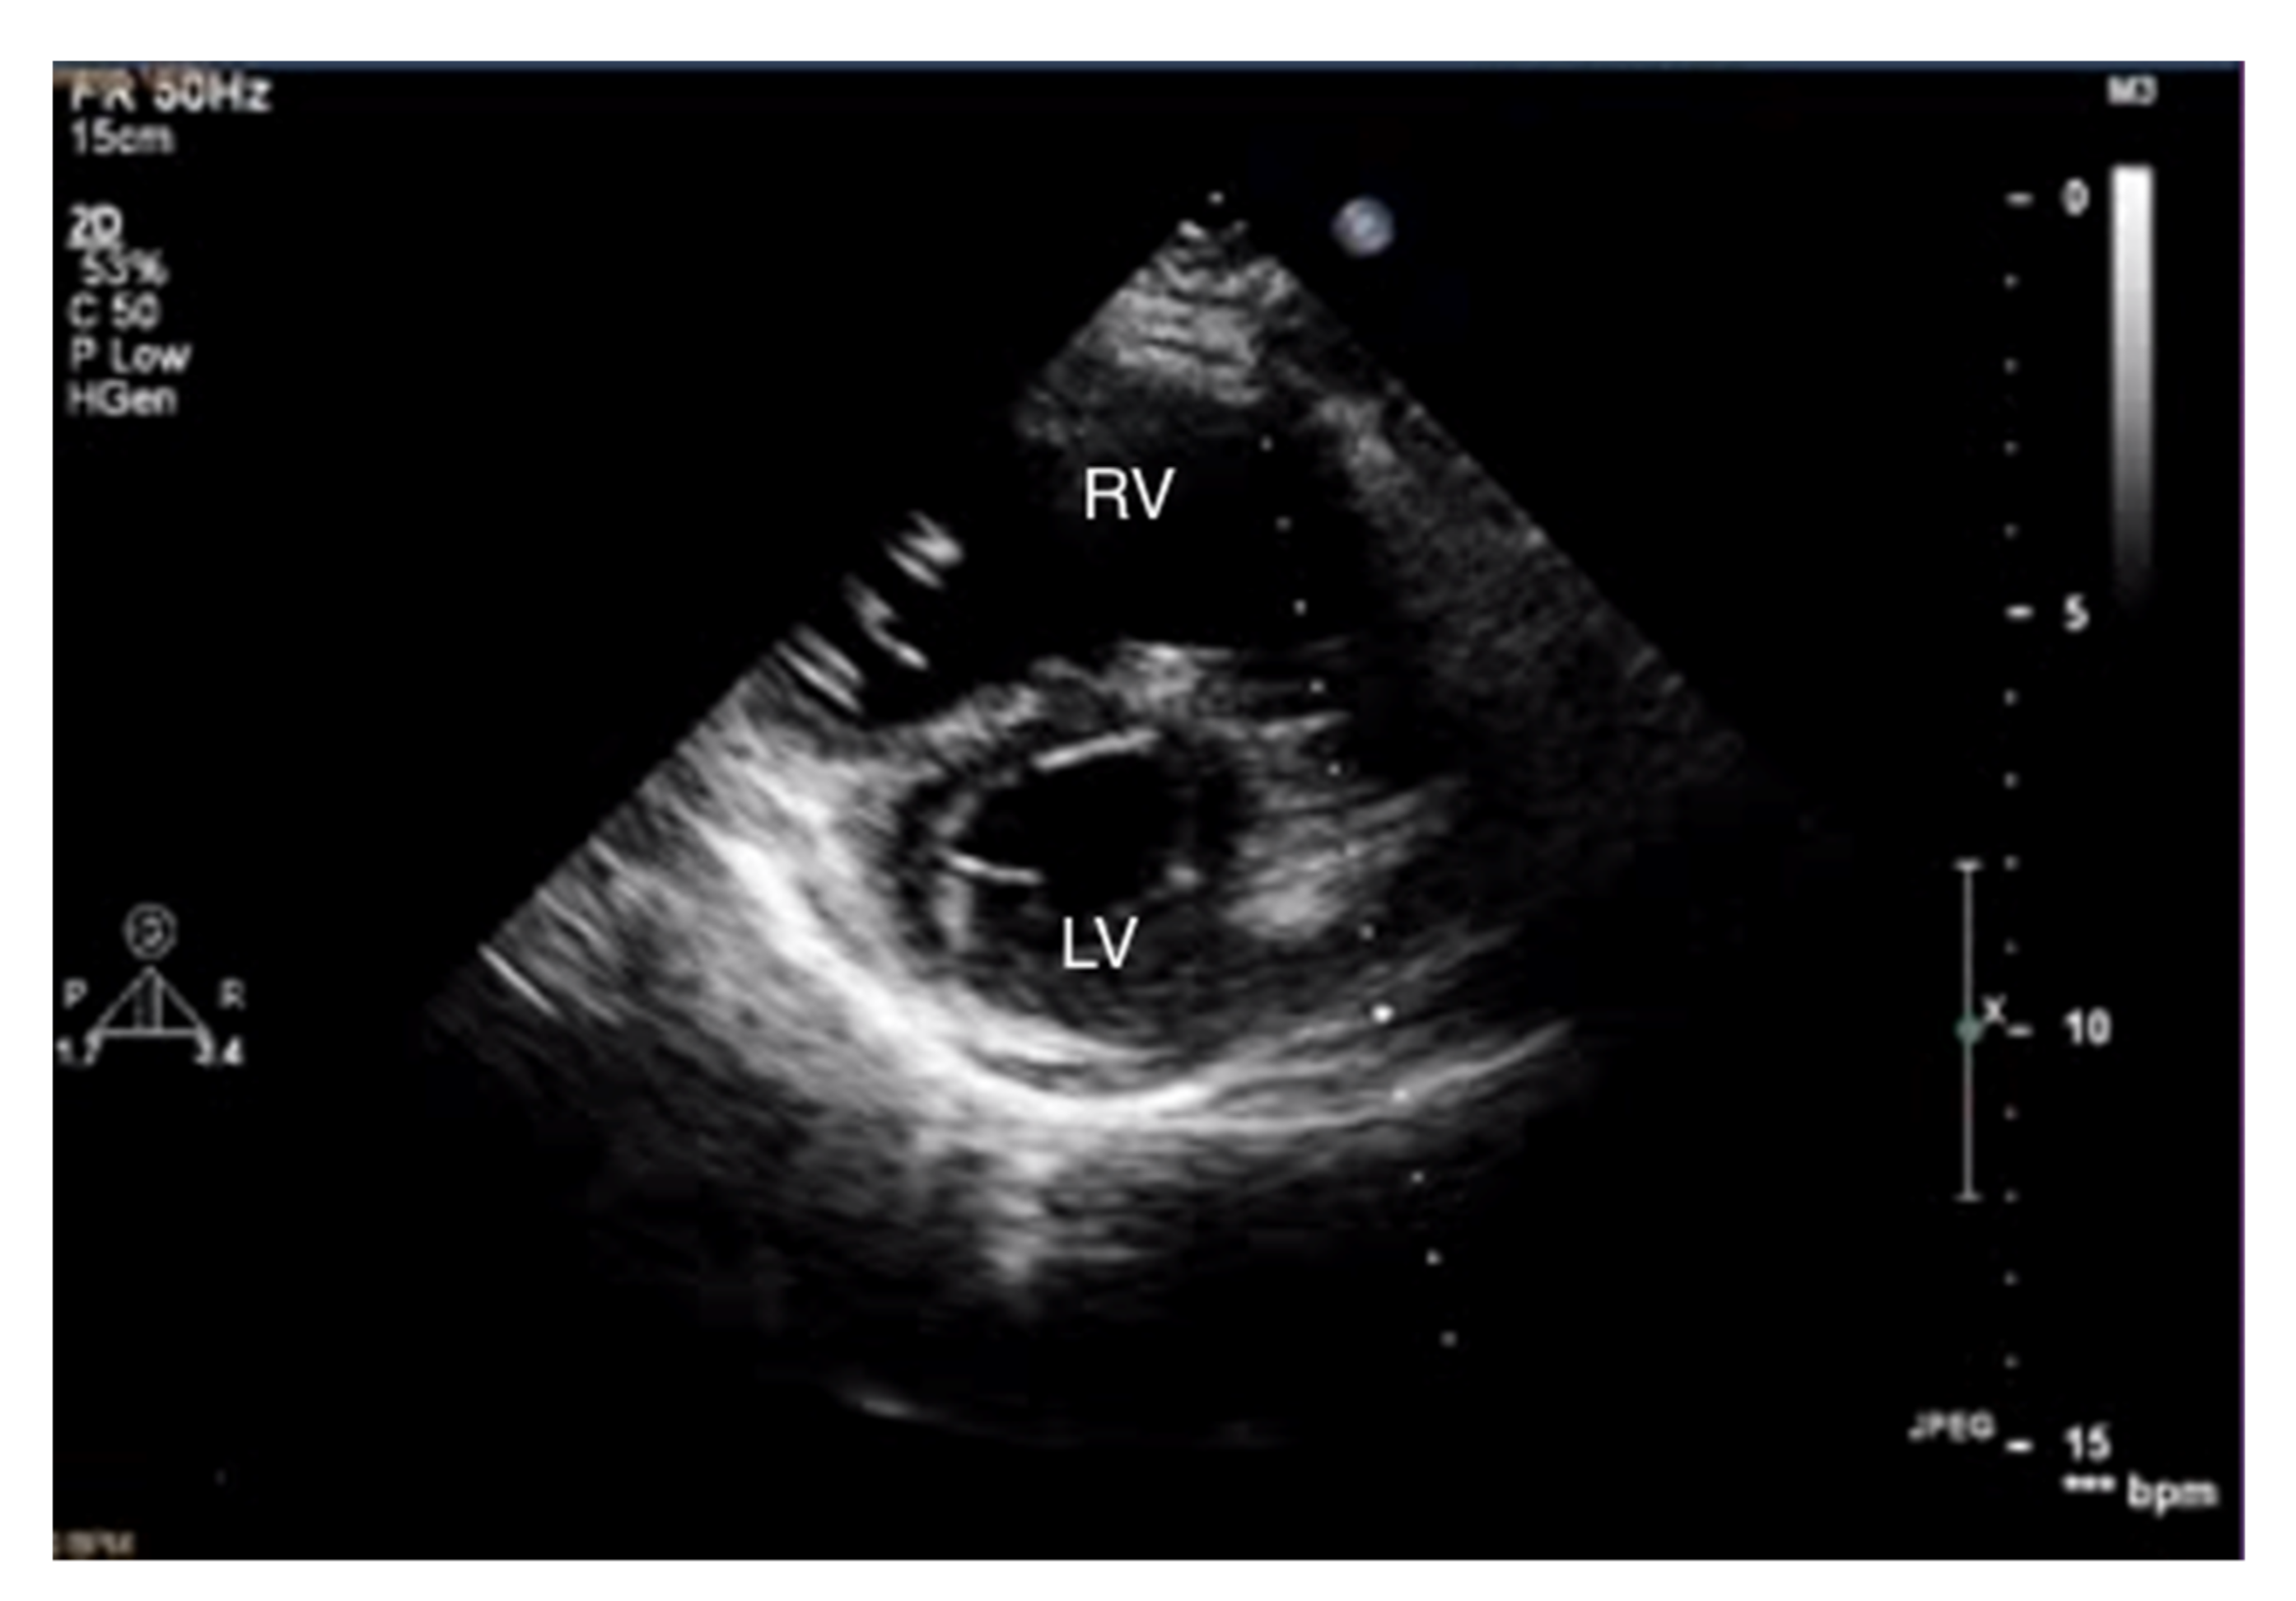

Figure 2.

Enlarged right ventricle. 2D-TTE, parasternal short-axis view (PSAX). RV: right ventricle, LV: left ventricle.